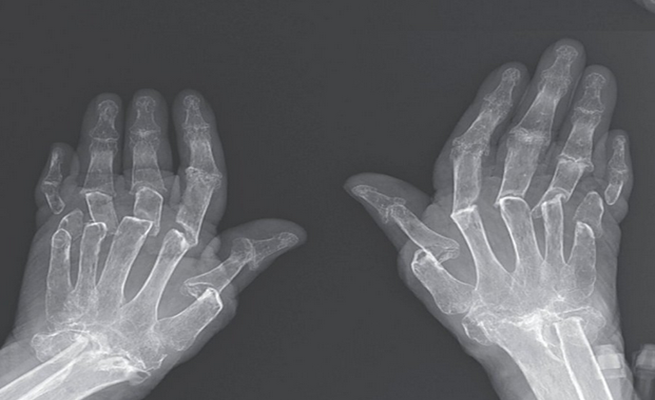

وكشفت الصور الشعاعية ليدي المريضة عن مدى الضرر الذي أصابها، حيث بدت أصابع اليدين والرسغ والساعد السفلي، متآكلة، كما لو أن كميات كبيرة من الأنسجة اختفت.

وعزا الأطباء فقدان الأنسجة إلى عملية تسمى انحلال العظم، والتي تسبب “إعادة امتصاص” العظام بواسطة خلايا تسمى الخلية ناقصة العظم أو هادمة العظم.

وفي حالة المريضة البالغة من العمر 69 عاما تسببت الأضرار الناجمة عن فرط نشاط الخلايا هادمة العظم، في تقلص عظامها نظرا لأن هذه وظيفة هذه الخلايا بالأساس هي هضم العظم الزائد وغير المفيد.